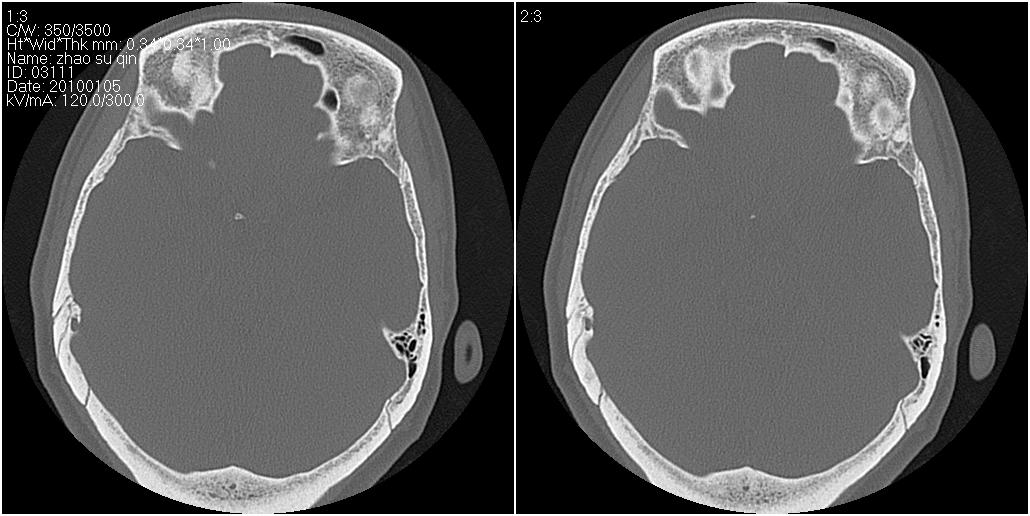

标题: CT24015:一个头部外伤患者进行鉴定,除了左侧筛板骨折,哪

1)左侧筛板骨折。2)双侧筛窦炎症(或积血)。

左眶下裂部好像有骨折 似有小碎骨片